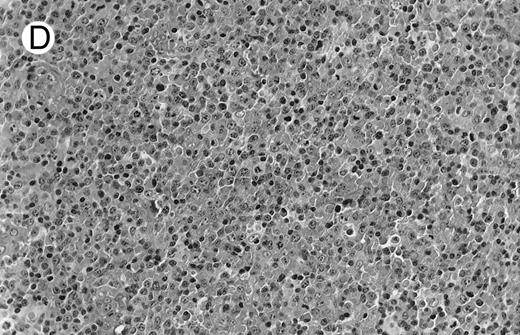

Low-grade marginal zone B-cell lymphoma (MZL; REAL classification)9 comprised the largest number of cases (n = 12). Nine of them were low-grade MALT type lymphomas involving parotid, stomach, bronchus, buccal mucosa, and skin. The histological pattern was relatively homogeneous, showing diffuse lymphoid infiltrates that included small lymphocytes with round nuclei or with plasma-cell differentiation and/or centrocyte-like cells with indented nuclei (Fig 1A). Lymphoepithelial lesions were observed in each case, regardless of the tissue involved (Fig 1B). Monocytoid cells characterized by a larger cytoplasm and a slightly irregular nucleus were mixed with centrocyte-like cells in 2 cases of MALT lymphoma arising in the parotid (cases no. 3 and 15). There were also scattered occasional large cells (centroblast or immunoblast). In cases no. 3, 6, and 15, remnants of germinal centers with partial follicular colonization were observed (Fig 1C). Beside these 9 low-grade-type mucosal lymphomas, 3 nodal lymphomas (cases no. 8, 10, and 14) had histological features similar to that of low-grade MALT type lymphoma because they showed a typical lymphoplasmacytoid infiltration with a variable proportion of blasts. In 2 cases, the presence of numerous immunoblasts or centroblasts, mixed with small lymphoplasmacytoid cells or plasma cells, indicated an evolution to a more aggressive lymphoma (Fig 1D). The third nodal lymphoma showed a small lymphocytic or lymphoplasmacytoid diffuse infiltrate associated with intrasinusal large nests of monocytoid cells. This histological picture is characteristic of monocytoid B-cell lymphoma (MBLC; Fig 1E).

NHL associated with SS (hematoxylin-eosin stains). (A) Case no. 13. Low-grade B-cell lymphoma of MALT type in the stomach, composed mainly of centrocyte-like cells with a few small lymphocytes and plasma cells. (B) Case no. 15. Low-grade B-cell lymphoma of MALT type in the parotid. Lymphoepithelial lesions are numerous, surrounded by centrocyte-like cells. (C) Case no. 6. Remnants of a germinal center in a low-grade B-cell lymphoma of MALT type in the parotid.

(D) Case no. 10. Immunocytoma in lymph node. The infiltrate is composed of small lymphocytes, plasma cells and blasts. (E) Case no. 14. Monocytoid B-cell lymphoma in a cervical lymph node with a monocytoid component located in dilated sinuses.